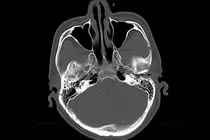

Hình ảnh tổn thương xương sọ trên phim chụp - Ảnh BVCC

Kết quả thăm khám và chẩn đoán hình ảnh cho thấy gãy xương sọ phức tạp nhiều mảnh di lệch, kèm xuất huyết nội sọ, dập não khu trú vùng trán, phù não và nguy cơ tổn thương màng cứng, nhu mô não.

Bệnh nhi gãy xương sọ phức tạp nhiều mảnh di lệch, kèm xuất huyết nội sọ, dập não khu trú vùng trán, phù não và nguy cơ tổn thương màng cứng, nhu mô não.